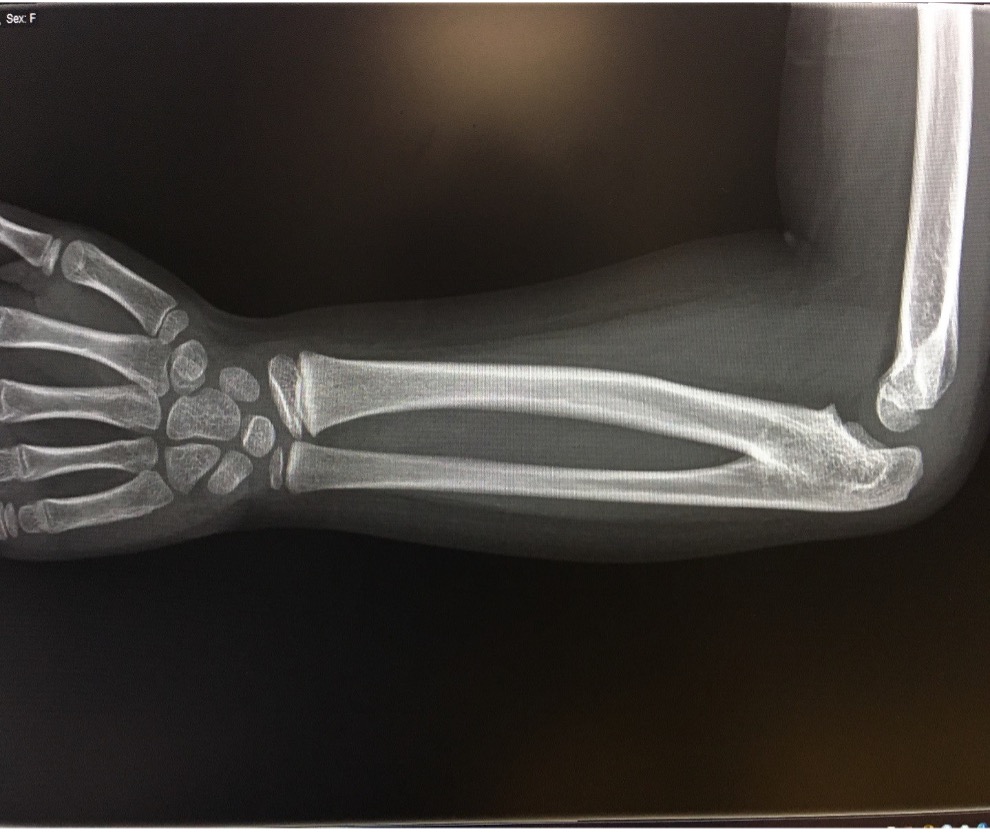

Some mild tenderness was noted upon deep palpation of the lateral elbow. The patient also had clinodactyly of the fifth phalange bilaterally. No other skeletal abnormalities were noted. A 3-view radiography scan of the elbow was conducted, results of which showed bilateral radioulnar synostosis (Figures 1-4). No wrist abnormalities were identified.

Figure 1. A radiology scan of the patient’s upper left extremity, lateral view.

CRUS has been described based on radiological classifications, the anatomical location of synostosis, and how it influences functionality. The most common radiological classification of CRUS, described by Cleary and Omer, is based on the appearance of the synostosis and reduction of the radial head (Table).6,10 Type I occurs with no osseous synostosis but a reduced radial head. Type II occurs with bony synostosis. Type III occurs with osseous synostosis with a hypoplastic and posteriorly dislocated radial head. Type IV occurs with short osseous synostosis with an anteriorly dislocated radial head. The radiological findings in our patient depicts a type II congenital radioulnar synostosis (Figure 1). Another description was explained by Wilkie, for which type I shows a connection between the radius and ulna occurs at the medullary canal; with type II, the fusion occurs distal to the proximal radial epiphysis and the radial head is dislocated anteriorly or posteriorly.4 A third description, which pertains to just the proximal radioulnar synostosis has also been portrayed.11 In type I, there is an absence of the radial head followed by complete radioulnar synostosis. In type II, the proximal part of the radial head is present but often deformed, and fusion occurs at the neck of the ulna. In type III, the head of the radius is always deformed and subluxed with synostosis occurring at the proximal area of the interosseous bones.